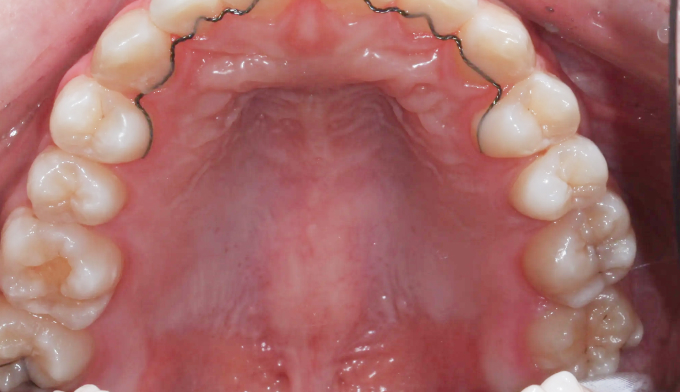

어금니가 선천적으로 없는 경우, 어금니 사이에 공간이 유지된 채 악골의 성장이 완료됩니다. 벌어진 어금니 공간은 음식물이 잘 끼게 되므로, 충치가 생길 수 있는 가능성이 높아지고 냄새가 나기도 합니다.

이때, 이러한 공간을 벌려서 임플란트를 식립하는 방법이 우선적으로 고려됩니다. 하지만 후방에 사랑니가 위치한 경우, 임플란트 대신 사랑니를 당겨서 쓰게 되면 내 치아를 살리면서 동시에 임플란트라는 인공 구조물을 식립하지 않아도 되기 때문에 교정치료가 훨씬 효율적인 치료가 됩니다.

교정기간은 8개얼 소요되었고, 안적적으로 유지하기 위해 일정기간동안의 유지장치 착용이 필수입니다.